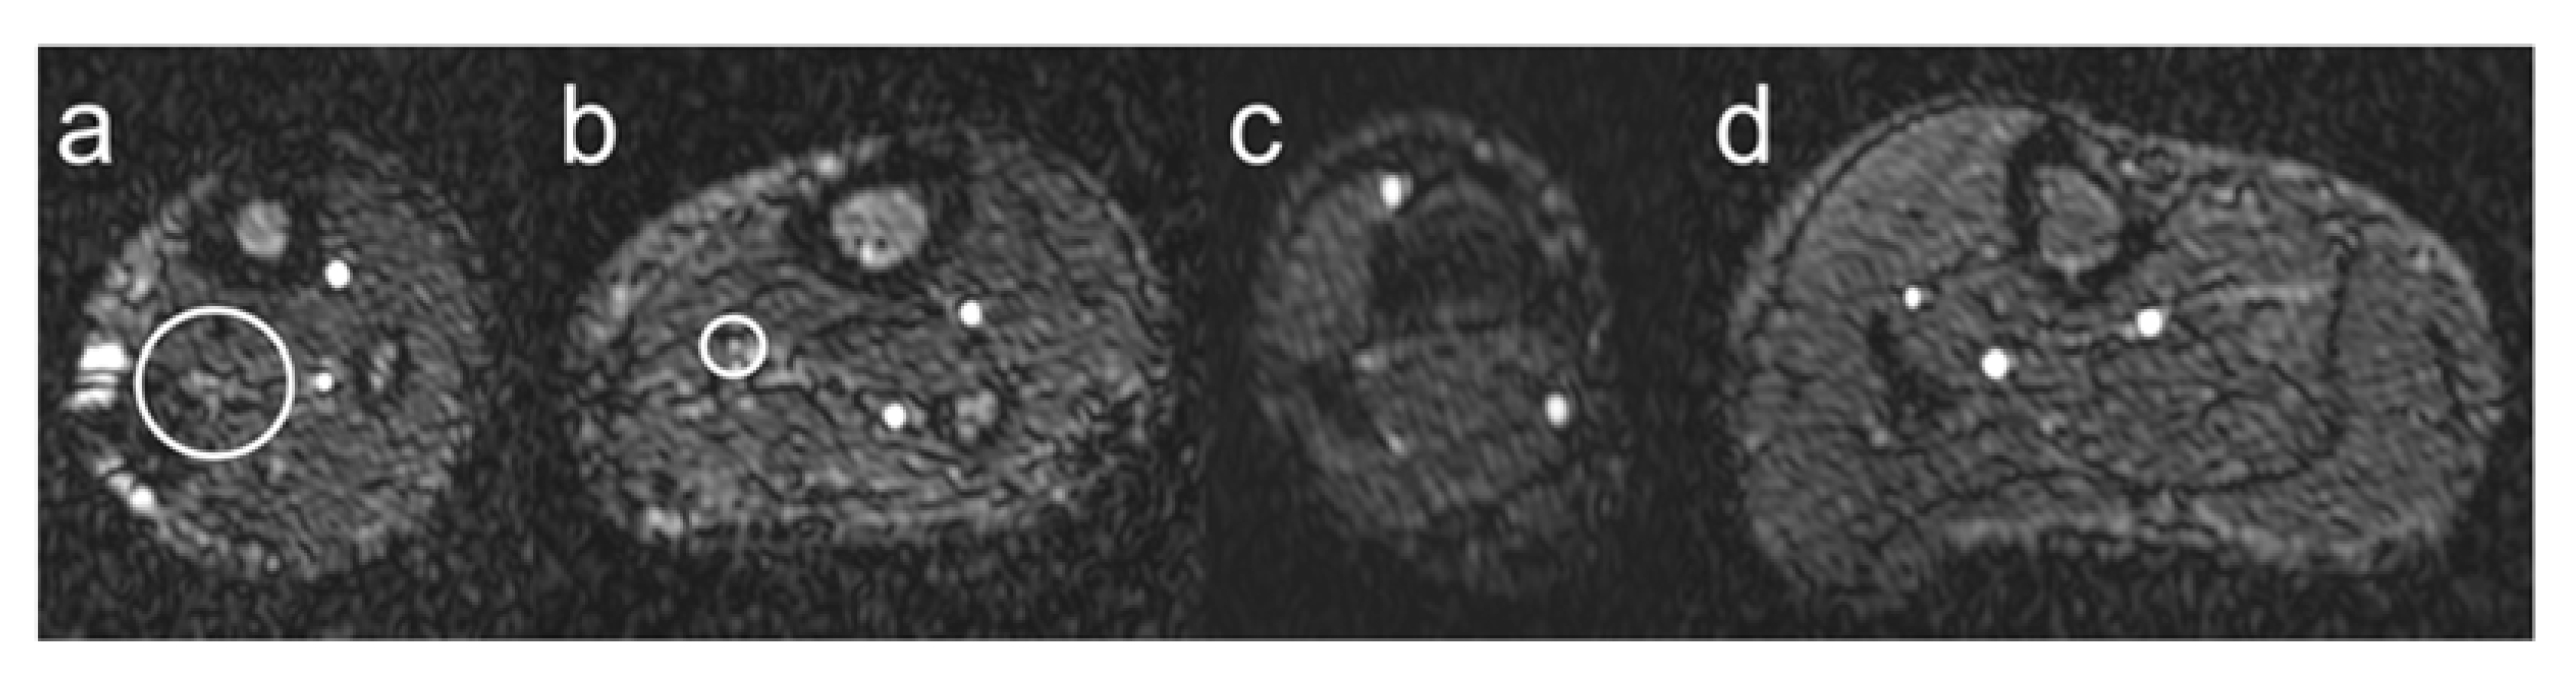

Figure 2.

Vessel visualization. Schematic illustration of the visualization of lower leg arteries based on the grading scoring system introduced in Section 2.3. Grade 1 is shown in panel (a), grade 2 in panel (b), grade 3 in panel (c), and grade 4 in panel (d). The white circles indicate lower leg arteries with barely visible lumen (grade 1) and poorly defined vessel boundaries (grade 2).

- Grade 1: Nondiagnostic, barely visible lumen rendering the segment.

- Grade 2: Fair, ill-defined vessel borders with suboptimal image quality for diagnosis.

- Grade 3: Good, minor inhomogeneities not influencing vessel delineation.

- Grade 4: Excellent, sharply defined arterial borders with excellent image quality for highly confident diagnosis.